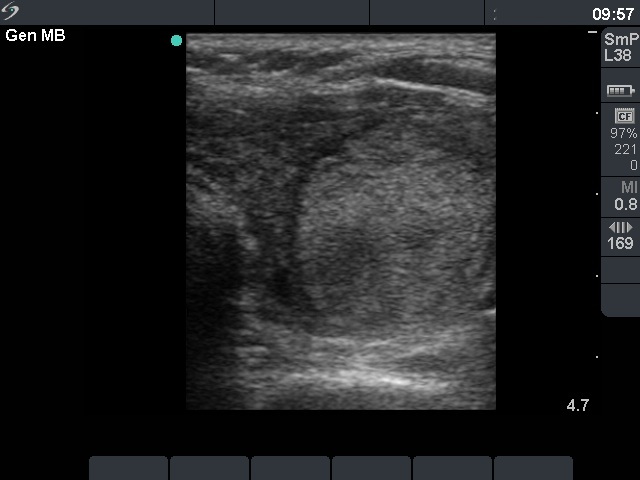

First examination - before surgery (1st row of images)

Clinical presentation: a 47-year-old woman was referred for evaluation of nodular goiter. She noticed a lump in the left lobe for a month.

Palpation: a large nodule in the left lobe.

Results of blood test: euthyroidism (TSH 3.31 mIU/L).

Ultrasonography: the right thyroid was echonormal and contained hypoechogenic areas. The left lobe was moderately hypoechogenic. There was a large hyperechogenic nodule in the left thyroid. The nodule displayed halo sign and type 2 vascular pattern.Cytology resulted in benign lesion.

Final diagnosis. Benign nodule in the left thyroid. Chronic lymphocytic thyroiditis. Left lobectomy was advised because of the size of the nodule.

Histopathology disclosed benign hyperplastic nodule and chronic lymphocytic thyroiditis.

Before surgery the thyroids presented unequivocal signs of lymphocytic thyroiditis: the left thyroid was moderately hypoechogenic while the right displayed hypoechogenic spots within an echonormal background.